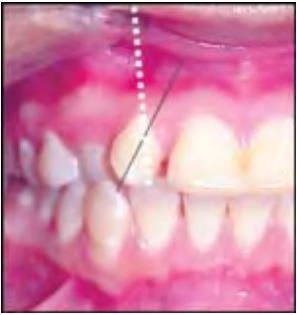

1.5) KHỚP CẮN THẤP

Răng nằm dưới mặt phẳng nhai và thấp hơn so với những răng khác trên cung hàm

1.6) KHỚP CẮN CAO

Răng nằm cao hơn mặt phẳng nhai so với những răng khác trên cung hàm